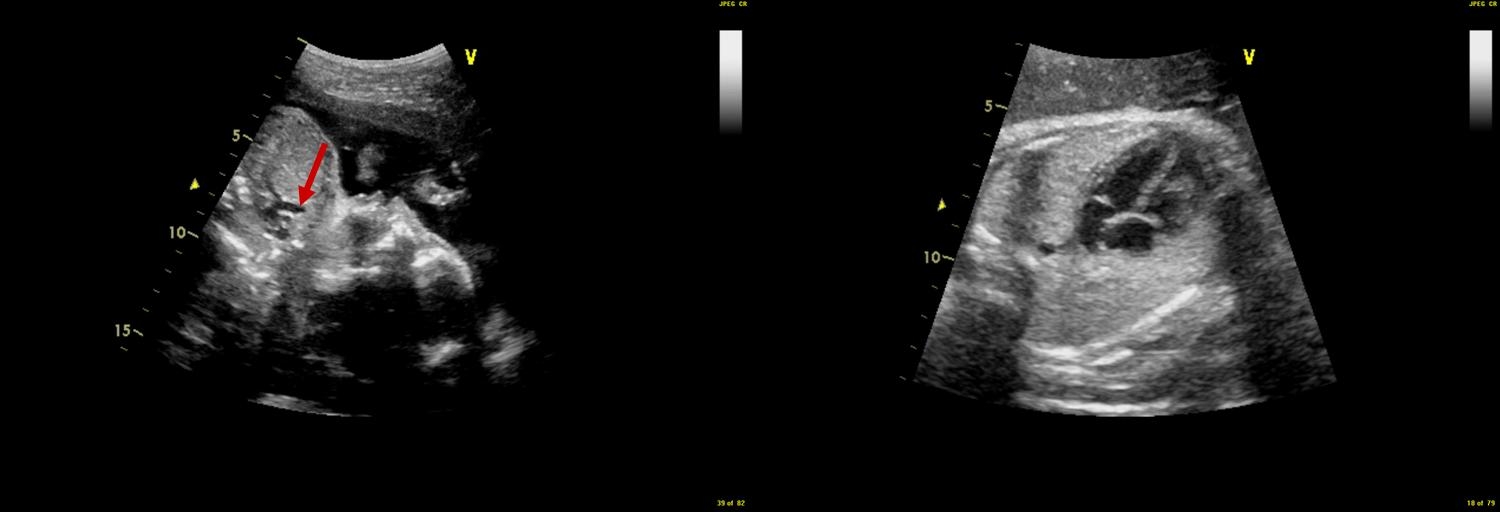

A fetal echocardiogram is a detailed ultrasound performed of the baby's heart before the baby is born. A small camera called a transducer is placed on the pregnant mother's abdomen and sends out ultrasonic sound waves. The ultrasound waves bounce off the baby's organs, including the heart and are sent back to the camera which then creates a moving picture of the different parts of the heart for the doctor to evaluate. The sound waves can also detect blood flow throughout the baby's heart. This enables the doctor to evaluate the structure and function of the fetal heart.